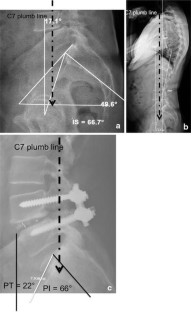

Significant improvement toward more normal values for PT and SS in relation to PI was observed after surgery. Pelvic incidence was unaffected by surgery. Correction of the spinosacral angle shows that the anterior tilt with anterior sagittal imbalance due to spondylolisthesis may be corrected by reduction and fusion of the slipped level. Functional outcome was satisfactory with a statistically significant difference between preoperative values and final follow-up values. The sub-group of patients with insufficient restoration of sagittal balance parameters had less good outcomes than the others.

Surgical management of low- and mid-grade isthmic spondylolisthesis showed good clinical outcome with restoration of correct values for the pelvic position-dependent parameters, i.e., pelvis tilt, sacral slope, C7 plumb line position and SSA.